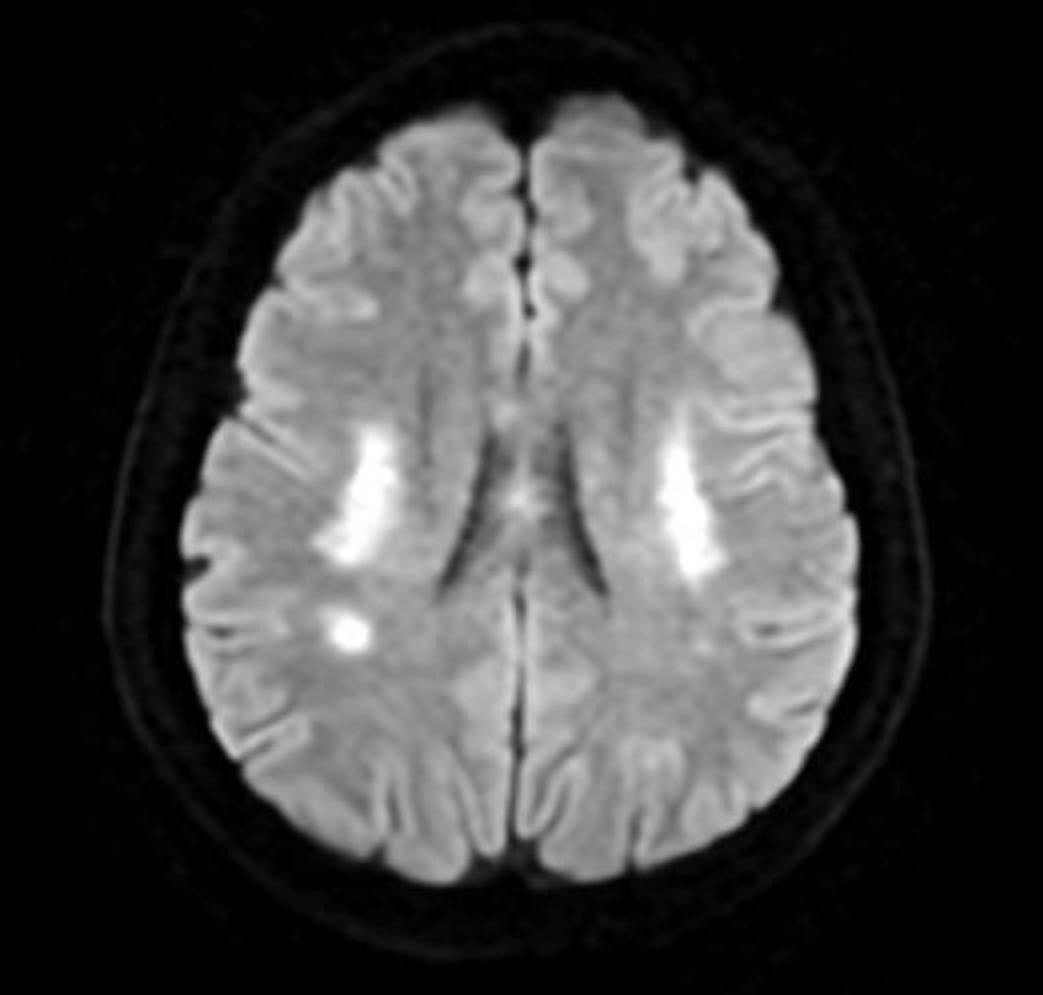

Trên hình ảnh kiểm tra, bác sĩ ghi nhận tình trạng tổn thương não xảy ra ở người bệnh (ảnh: BSCC)

PGS Huy Thắng cho biết, ngay khi nhập viện, người bệnh được chụp MRI não. Hình ảnh cho thấy tổn thương não xảy ra ở hai bên trung tâm bán bầu dục và vùng lồi thể chai. Các thăm dò mạch máu não không ghi nhận tình trạng tắc hay hẹp các động mạch lớn. Dựa trên lâm sàng và hình ảnh học, các bác sĩ chẩn đoán bệnh nhân bị nhồi máu não cấp vùng trung tâm bán bầu dục hai bên và lồi thể chai.

“Vùng trung tâm bán bầu dục, theo Louis Caplan - Giáo sư Thần kinh học tại Trường Y Harvard chính là vị trí ưa thích của những huyết khối nhỏ nhắm đến, đặc biệt khi bệnh nhân có tổn thương nhiều vùng chi phối mạch máu (trung tâm bán bầu dục 2 bên và lồi thể chai thuộc chi phối hệ cảnh - não giữa 2 bên và động mạch não trước hoặc động mạch não sau). Ngoài thuyên tắc huyết khối, trung tâm bán bầu dục là vùng giáp ranh cũng là vị trí tổn thương phù hợp với cơ chế giảm tưới máu”- PGS Huy Thắng giải thích thêm.